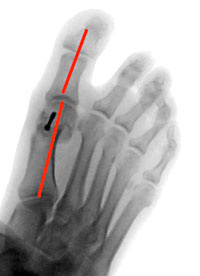

hallux-operation-eine-100-prozentige-sache-3

Abb. 3

Gelenkferne Korrektur